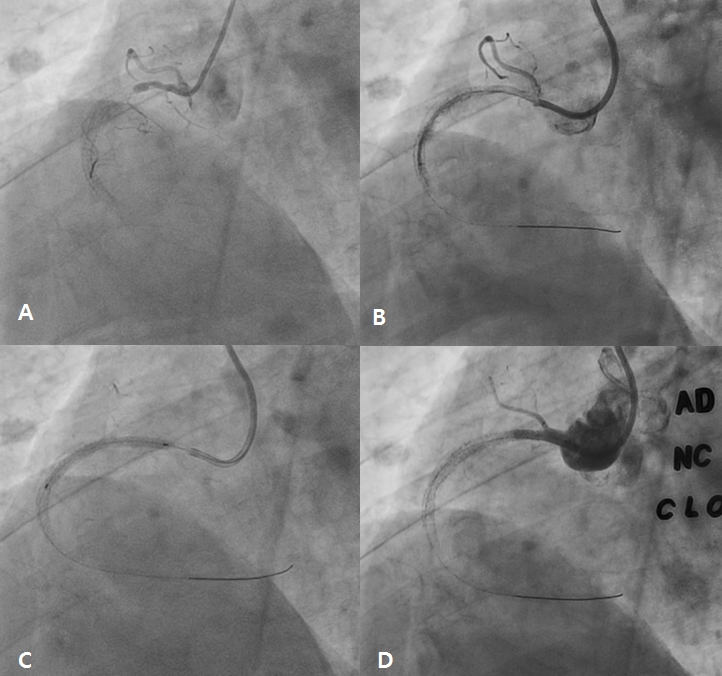

A 78 year-old male visited the outpatient department of Chonnam National University Hospital with intermittent chest pain for 4 months. He underwent percutaneous coronary intervention (PCI) for acute myocardial infarction (AMI) using bare metal stent in the proximal right coronary artery (RCA) 8 years ago. After that, he had undergone repeat intervention using drug eluting ballooning 7 years ago and PCI for mid RCA 6 years ago due to repeated in-stent restenosis (ISR) in RCA. He was treated with dual anti-platelet therapy of aspirin (100 mg daily) and clopidogrel (75 mg daily). Recently, he suffered from chest pain intermittently and was taken to our hospital. The 12-lead electrocardiogram showed normal sinus rhythm and left bundle branch block (no interval change) (Figure 1), and the level of cardiac enzymes were within normal range. He underwent elective coronary angiography (CAG), and it revealed chronic total occlusion in proximal RCA (Type IV ISR) (Figure 2A) with moderate stenosis in proximal left descending artery (LAD). We considered to do staged PCI for proximal LAD. After wiring into RCA with microcatheter backup, stepwise ballooning using 1.5 mm and 2.5 mm diameter balloon was done. Then, a 3.5 x 38 mm everolimus-eluting stent (Xience Alpine®) was implanted at proximal RCA (Figure 2B). Just after stenting with up to 10 atmospheres, no reflow below the lesion site was shown on follow-up CAG (Figure 2C). Coronary blood flow was not restored after intracoronary adenosine, nicorandil and glycoprotein IIb/IIIa inhibitor bolus injection in RCA (Figure 2D). Although we did additional ballooning from distal to proximal RCA again and again (Figure 3A), follow-up CAG showed still no reflow in RCA (Figure 3B). So, we infused intracoronary adenosine and nicoradil using microcatheter from proximal to distal RCA selectively (Figure 3C). Final CAG showed improved antegrade flow (TIMI III) in RCA without significant residual stenosis (Figure 3D). He was transferred to coronary care unit and monitored with anticoagulation for 1 day.

Figure 3. After additional ballooning from distal to proximal right coronary artery (RCA) (A), there was still no-reflow in RCA (B). Intracoronary adenosine and nicorandil was selectively infused using microcatheter from distal to proximal RCA (C). Final coronary angiography showed improved antegrade flow in RCA without significant residual stenosis (D).